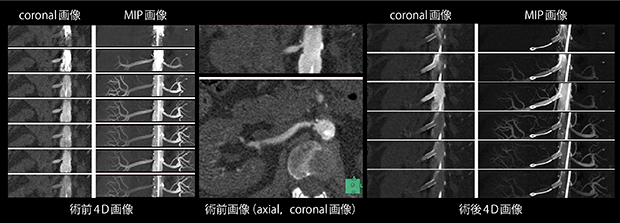

腎動脈における超低造影剤量4次元イメージング

垣見明彦(大阪市立大学医学部附属病院中央放射線部)

【背 景】65歳,女性。難治性高血圧の加療を目的に他院より紹介。術前の血清クレアチニン値は2.96mg/dL,eGFRは13.2mL/min/1.73m2であり,高度な腎機能の低下を認めていた。術前のMRAでは右腎動脈起始部に狭窄を認め,腎動脈ステント留置術を施行した。本検査は腎動脈ステント留置術の術中に,腎動脈狭窄の診断と腎動脈ステントの拡張評価を目的に施行した。

【所 見】術前撮影では,右腎動脈起始部にプラークを伴う狭窄を認める。術後撮影では,ステントは大動脈側にわずかに突出して留置されている。ステントの良好な拡張に加えて,内腔の開存も確認できる。

【訴求ポイント】高度腎機能低下症例のため,造影剤量を最大限に低減することが求められることから4次元撮影(DynMulti)を選択した。造影剤は高倍率に希釈し,腹部大動脈に留置したカテーテルより注入した。Dyn Multiにより得られた時間分解能の高い複数の時相から最適な造影効果が得られた時相を選択することで,被ばく線量は多めながらも,超低造影剤量にて腎動脈ステント留置術で求められる術前および術後評価を達成できた。腎機能の低下が著しい本症例では,術前の大動脈造影や術後DSA撮影は実施していない。造影剤使用量は術前撮影6mL,術後撮影4mLであり,手技全体では15mL(すべて原液換算)であった。